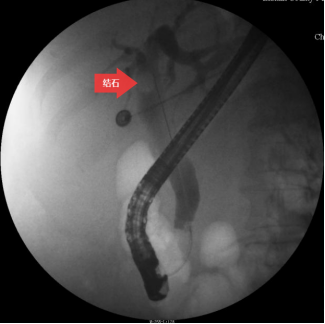

圖三:膽道造影

第三步:插管成功后,注入造影劑,造影顯示膽總管結石。(箭頭所指為膽總管結石)